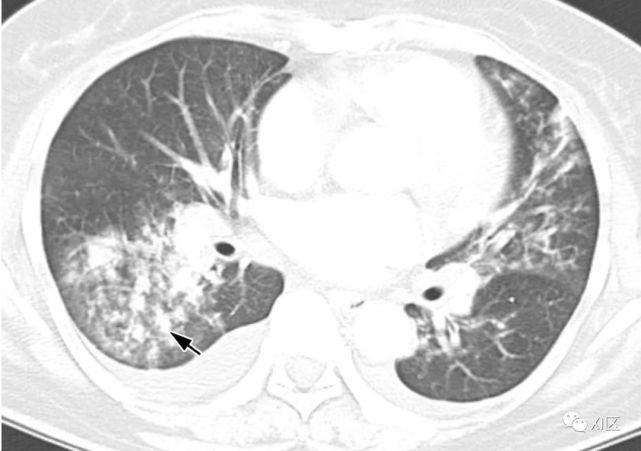

图16 58岁女性急性髓系白血病伴有发热,并发呼吸道合胞病毒肺炎。

(上) 初诊胸片显示双肺多发不规则结节状支气管周围气隙或GGO(箭头),少量双侧胸腔积液。在同一天在较低的气管水平(中)和叶间区水平(下)上获得的轴位胸部CT图像显示多个不规则的结节影和树芽征,沿支气管血管束斑片状实变,支气管壁轻度增厚。

Koo H J , Lim S , Choe J , et al. Radiographic and CT Features of Viral Pneumonia[J]. Radiographics, 2018, 38(3):719-739.